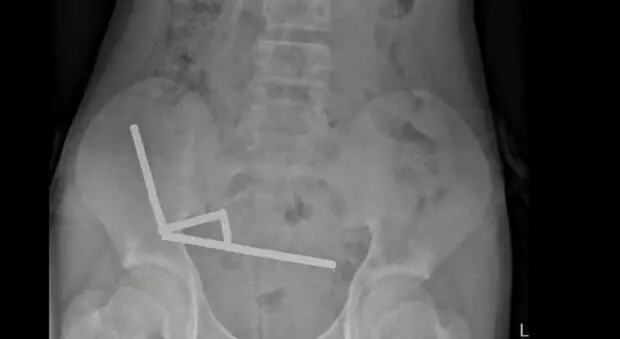

All'ospedale per forti dolori allo stomaco: il 13enne aveva ingoiato 100 magneti al neodimio acquistati su Temu

Un ragazzino di 13 anni ha rischiato la vita per aver ingerito circa un centinaio di magneti al neodimio acquistati sulla piattaforma di shopping online Temu - vietati dal gennaio del 2013 in...